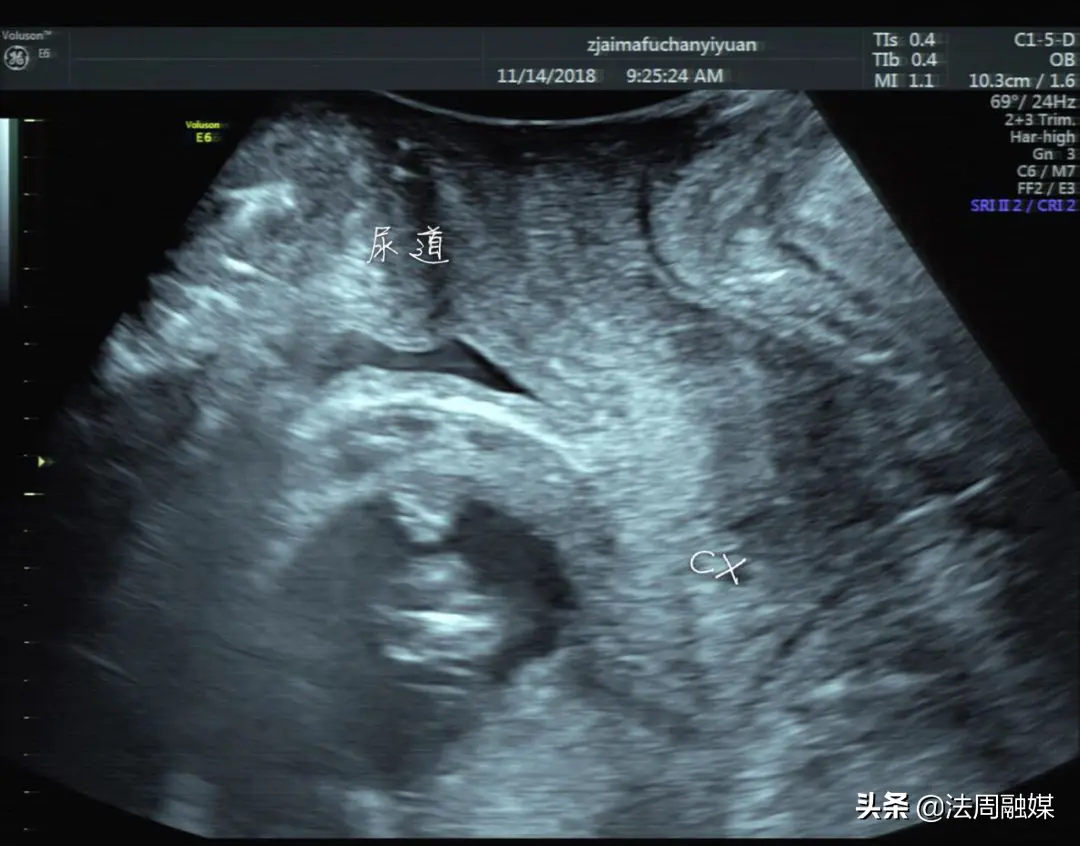

怀孕引流是什么

怀孕是许多女性人生中最珍贵的经历之一,但有时候,因为各种原因,一些女性需要选择引流来终止妊娠。那么,什么是怀孕引流呢怀孕引流,也称为流产,是一种可以在早期妊娠时终止怀孕的医学过程。它通常通过药物或手术方式进行,其中手术包括吸宫术和刮宫术。

药物流产通常在怀孕早期(7周以下)使用。它通过给予一种名为米非司酮的药物,刺激收缩,来导致流产。这种方法通常需要在医生的监督下使用,因为如果不正确使用,可能会导致出血或其他并发症。

手术流产则是通过在内部进行手术来终止妊娠。这种方法在妊娠早期和晚期都可以使用。与此同时,在晚期妊娠时,可能需要更复杂的手术程序,例如剖腹产。

需要注意的是,怀孕引流并不是一项轻松的过程,它需要医生和病人之间的沟通和协作。在某些国家,怀孕引流可能是非法的,甚至可能会导致刑事指控。因此,如果您需要进行怀孕引流,一定要找到一个合法、安全的医疗机构。

总结一下来讲,怀孕引流是一种终止妊娠的医学过程。它可以通过药物或手术方式进行。与此同时,应该意识到这是一种需要慎重考虑和咨询医生的过程。